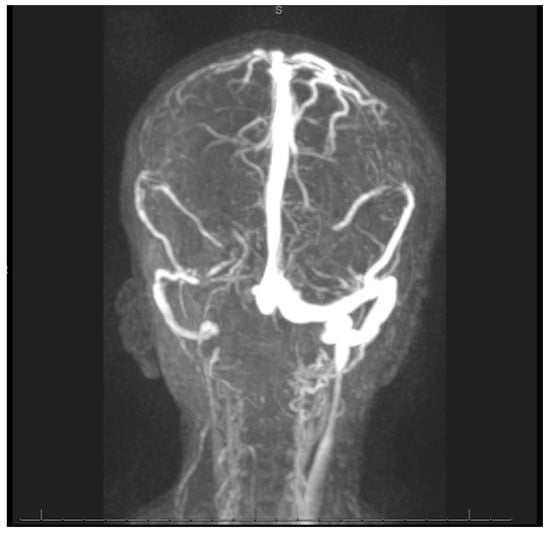

Magnetic Resonance Imaging (MRI), Magnetic Resonance Angiography (MRA), and Magnetic Resonance Venography (MRV): Magnetic resonance protocols indicated high T2 signal intensities extensively in the bilateral frontal, parietal, and occipital cortical and subcortical areas, with diffusion restriction. These findings were compatible with acute watershed infarctions with multifocal areas of embolic infarcts, suggestive of severe hypoxic–ischemic encephalopathy. The differential diagnosis included sepsis/septic shock and vasculitis, supporting a stroke workup. The right internal carotid long segment showed severe narrowing/occlusion, and the left internal carotid short segment showed narrowing. The differential diagnosis included vasculitis and sepsis/septic shock with dissection.

The right transverse sinus and internal jugular vein showed thrombosis.

MRA images: The images demonstrate a severe narrowing/occlusion of a long segment of the right internal carotid artery and a short segment of narrowing along the left internal carotid artery. Major intracranial cerebral arteries were patent. MRV images: The images demonstrate an occlusion of the proximal right transverse sinus and narrowing of the right internal jugular vein. The remaining superficial and deep cerebral veins and dural venous sinuses were patent.